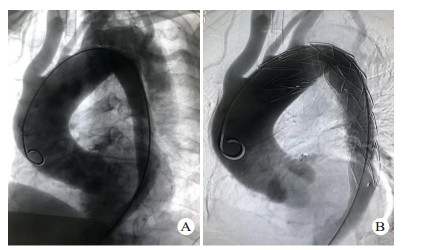

1 资料与方法 1.1 一般资料全组共14例,男性11例,女性3例,年龄23~71岁。急诊入院时间为伤后1~18 h。致伤因素包括车祸伤7例,高处坠落伤5例,重物砸伤1例,胸部击打伤1例; 车祸伤、高处坠落伤等钝性损伤患者不同程度伴有脑部受损,腹腔脏器破裂,血气胸或四肢、骨盆、肋骨、脊椎等骨折。其中伴血胸7例,肋骨骨折5例,四肢骨折3例,肝破裂1例,脾破裂1例,消化道穿孔1例,脑部受损1例,骨盆骨折1例,脊椎骨折1例。既往高血压病史5例。所有患者均由胸腹主动脉断层摄影血管造影(computed tomography angiography,CTA)明确诊断,均为Stanford B型主动脉夹层。夹层累及范围包括:胸主动脉夹层10例,胸腹主动脉夹层4例,肠系膜上动脉、肠系膜下动脉、左肾动脉受累各1例。本研究获得医学伦理委员会批准,编号:2018ER(A)037。治疗及检查均获得患者或家属知情同意。部分患者术前影像学资料见图 1。

| 图 1 患者男性,43岁,因车祸伤致胸背部疼痛入院,CTA诊断为TAD(A:普通胸片提示上纵隔明显增宽,隐约可见主动脉弓,左侧胸腔可见包裹性积液; B:胸部CT示降主动脉分层,可见真假腔,并可见左侧胸腔积液; C:胸腹部CTA提示自降主动脉起始部至前动脉起始部主动脉夹层,主动脉内径增宽; D:术后1年胸腹部CTA,支架位置良好,无移位,无内漏,无新发夹层或动脉瘤) |